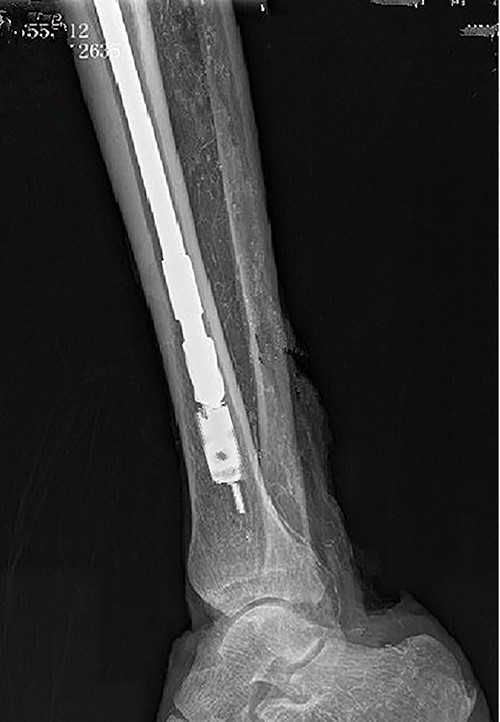

Preoperative X-ray films showing union of the right tibial fracture associated with a broken intramedullary nail remaining distal to the tibia.

A 48-year-old male patient was admitted for requesting removal of all internal implants in his body. He had a closed tibial shaft fracture caused by a collision 15 years prior and was treated with close reduction and intramedullary nailing fixation. Delayed healing occurred after the operation. A nail was broken at a distal locking screw hole. The fracture healed after plaster fixation for 3 months. The internal implant was removed 3 years after the fracture, but the distal end of the broken intramedullary nail could not be removed by the hook removal method and remained in the medullary cavity (Fig. 1). Both operations were performed in another hospital. One year prior to admission, the patient underwent open reduction and internal fixation in our hospital due to a fracture of the right distal radius, and the fracture healed after the operation. His function in the lower and upper limbs recovered well. It can be seen from the preoperative X-ray film that the remaining intramedullary nail was hollow; through measurement, it was known that the outer diameter of the broken nail was 10 mm, which was larger than the isthmus of the medullary cavity.